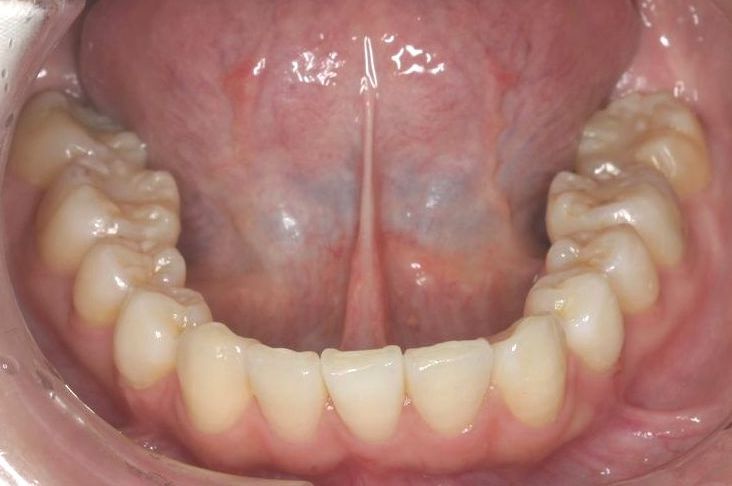

Case 2

主訴:  噛みにくい

診断:  アングルⅠ級 叢生

治療方針:

患者さんは26歳の女性で、上下顎の叢生による審美障害と咬合異常を訴えた。セファロ分析の結果、U-1 to FHおよびL-1 to Mandibularは1S.D.を超えて小さい値であった。その為、上下顎の叢生量は大きいが、上下前歯部の舌側傾斜による口元の落ち込みを防止する目的で、非抜歯で治療を行うことにした。

治療期間: 1年4カ月

費用:

診断費30000円、装置費用600000円、保定装置費用50000円、月1回の調整費4000円  (全て税別)

【 治療前 】

【 治療後 】